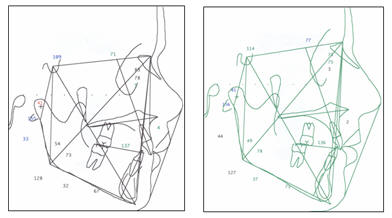

SUPERPOSICIONES

Son presentadas al

final adjunto a este trabajo

Los trazos

cefalométrico antes y después del tratamiento como sus

correspondientes valores degún Ricketts, Jarabak y McNamara se

presentan a continuación de manera integral.

|

1 DE

JULIO DEL 1996 |

23 DE

ABRIL - 2002 |

|

|

RICKETTS |

| |

|

|

1 DE

JULIO DE 1996 |

23 DE

ABRIL DEL 2002 |

|

|

JARABAK |

| |

|

|

1 DE

JULIO DE 1996 |

23 DE

ABRIL DEL 2002 |

|

|

McNAMARA |

|

|

SOBREPOSICIÓN ANTES Y DESPUÉS DEL TRATAMIENTO |